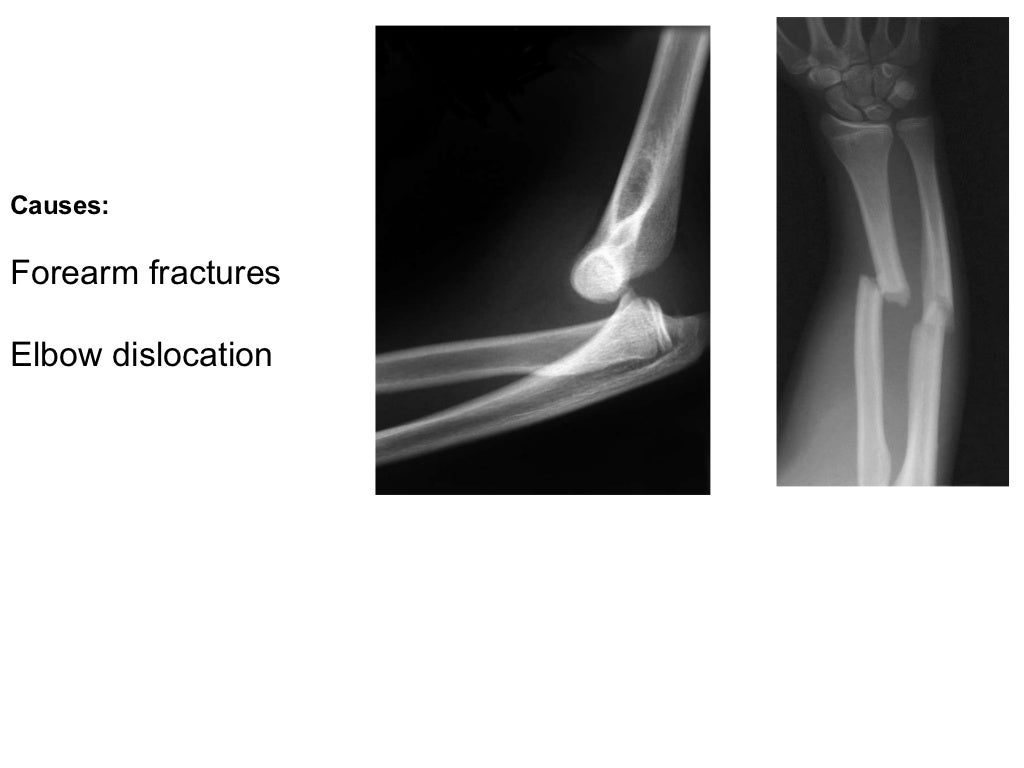

orthopedics.Radial nerve.(dr.baxtiar rasul) From slideshare.net